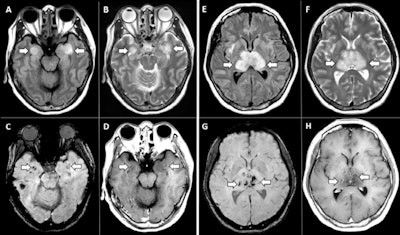

Researchers have found MRI to be useful for imaging the disease's neurological effects, which at the height of the pandemic researchers found can manifest as "cytokine storm syndrome" -- a condition in which the body's immune system prompts a flood of immune cells that can actually damage organs.

During the crisis, MRI has contributed useful data to the clinical knowledge base, demonstrating, for example, that COVID-19 patients with severe disease are at higher risk of encephalopathy, that 15% of competitive athletes who have recovered from the illness will show myocarditis on follow-up MRI, and that COVID-19's neurological manifestations vary depending on disease severity.